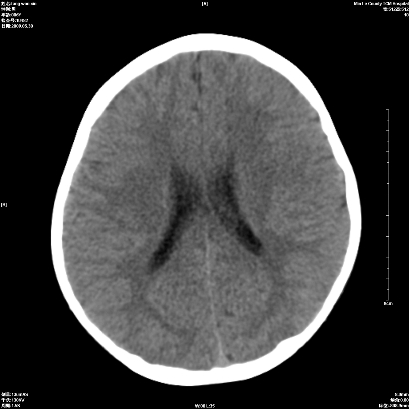

标题: 胆囊阴性结石ct图片

好啊!我有ct的插进来啊,楼主请允许噶。